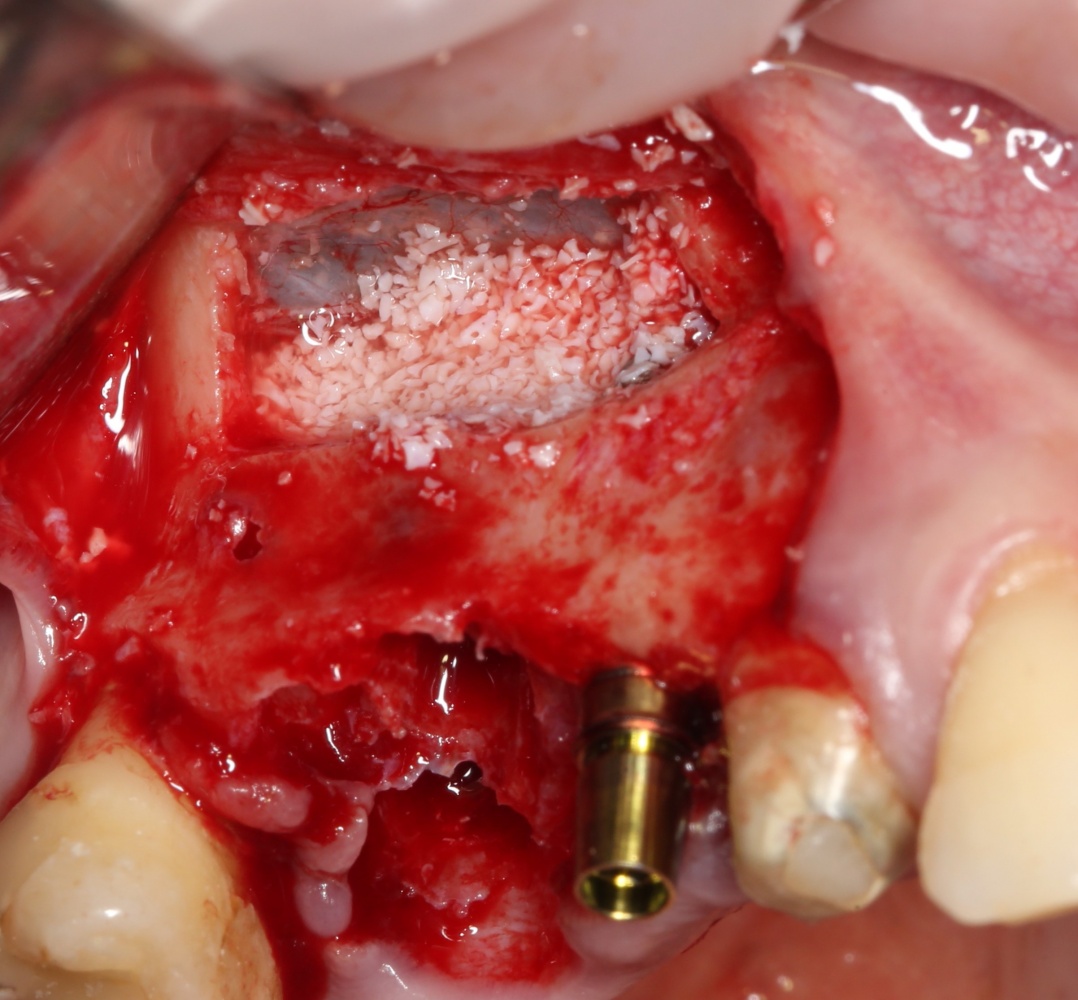

Простой синуслифтинг. Часть I.